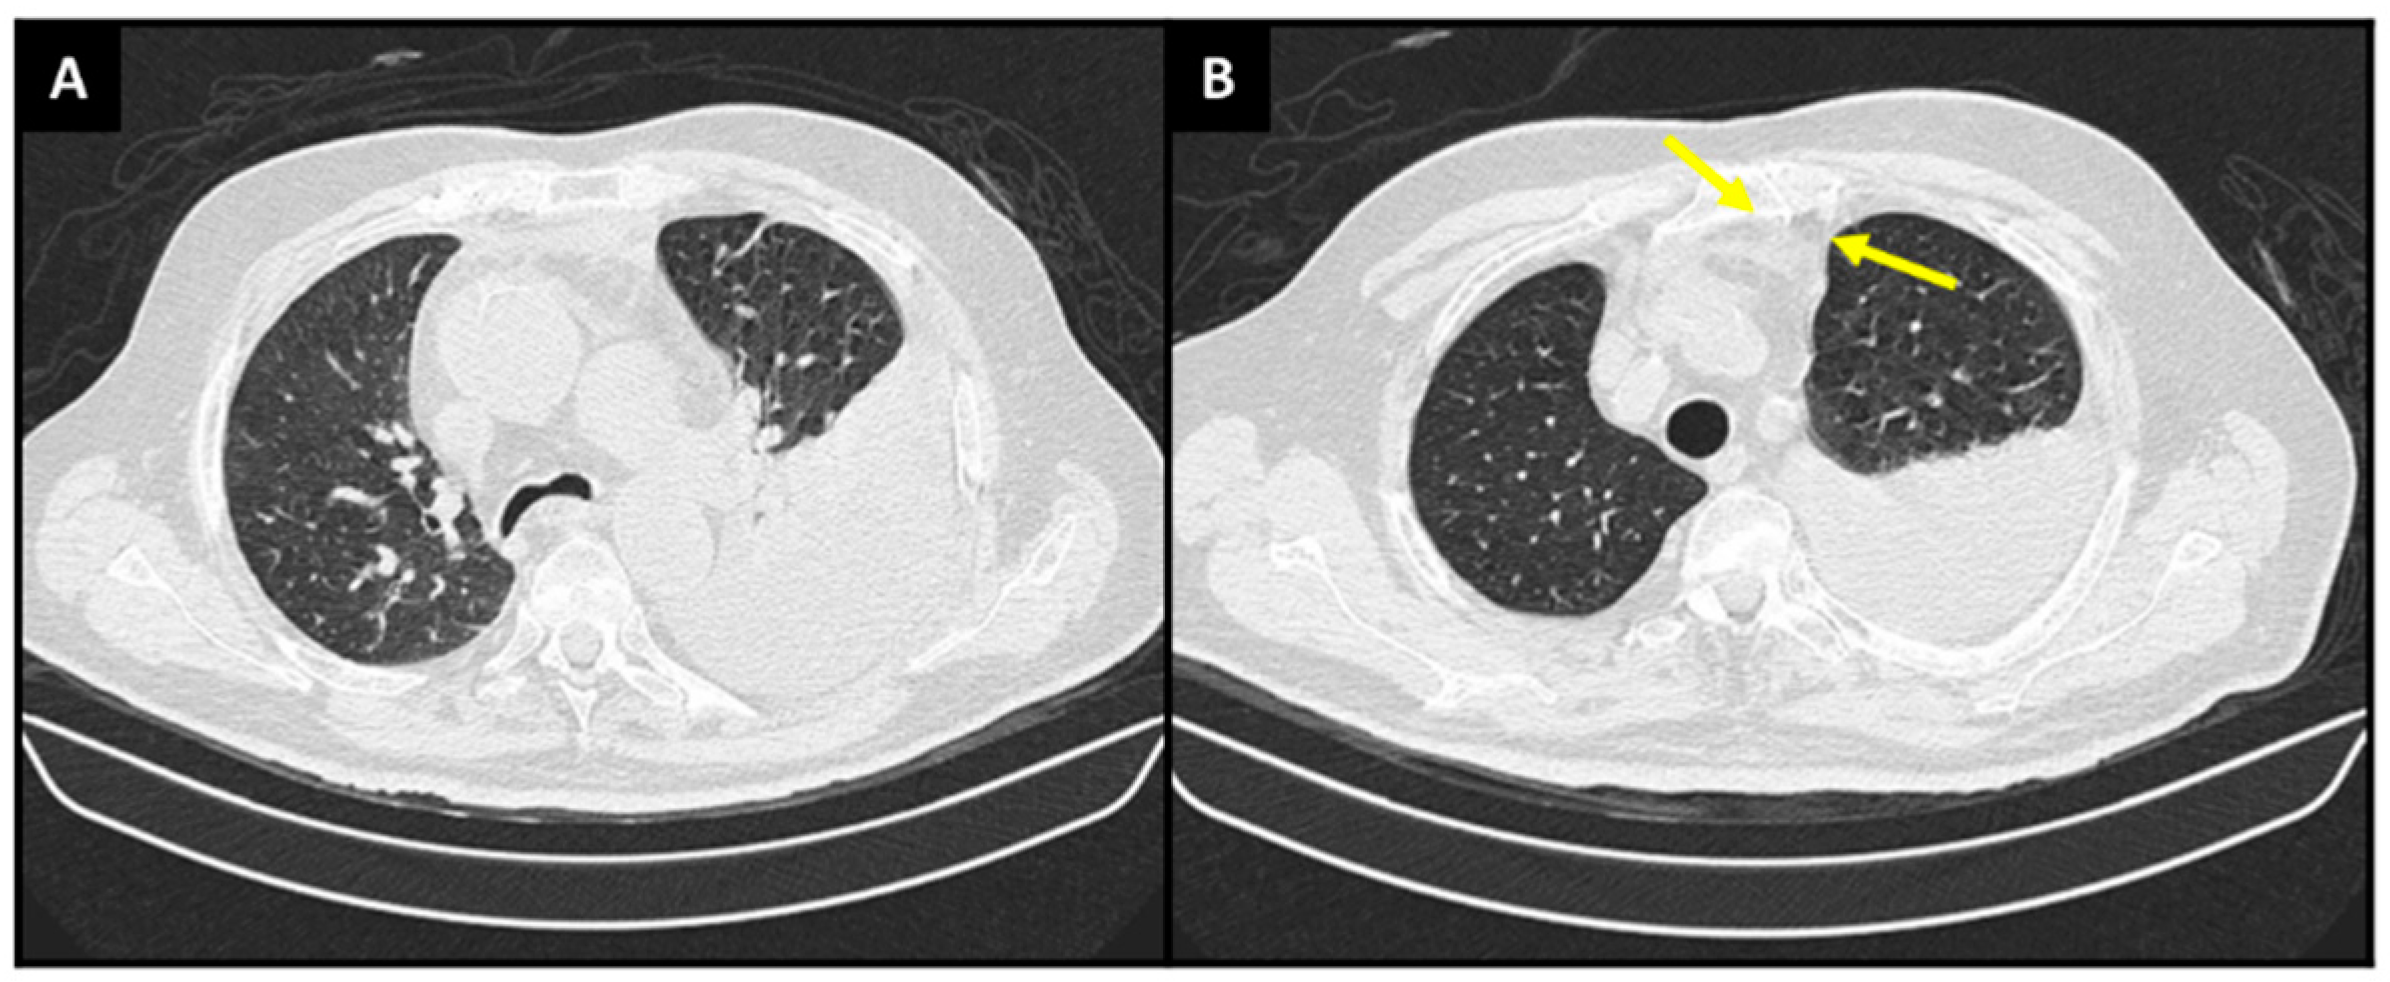

Diagnostics Free Full Text Primary Effusion Lymphoma A Rare And

https://www.mdpi.com/diagnostics/diagnostics-13-00370/article_deploy/html/images/diagnostics-13-00370-g001.png